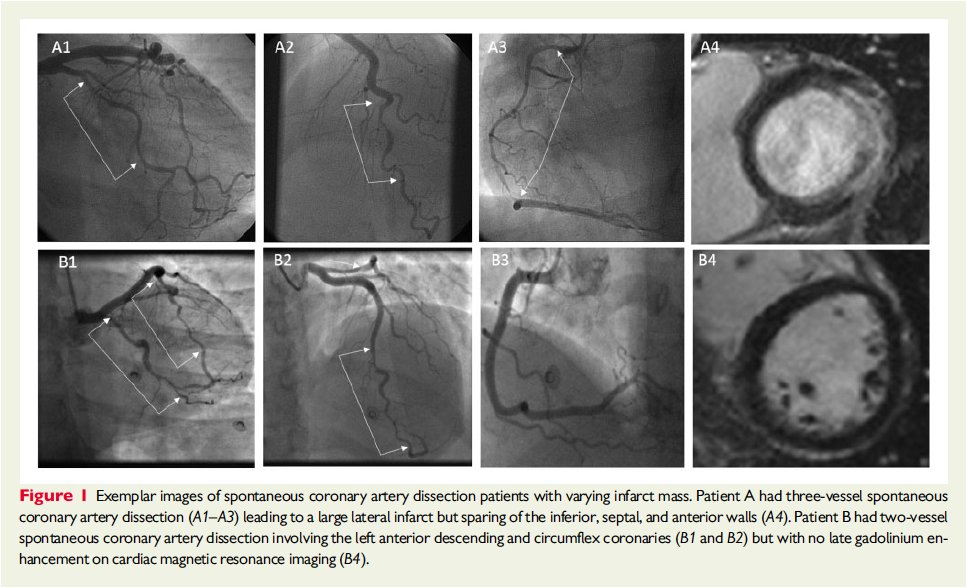

TAMAÑO DEL INFARTO EN DISECCIÓN CORONARIA 158

#SCAD vs 59 controles

#WhyCMR

Función sistólica VI preservada con poca reducción de FEY 57 ± 7.2% vs 60 ± 4.9%, P < 0.01

La mayoría de los infartos fueron pequeños. 39% sin LGE

Vía @ESC_Journals https://academic.oup.com/eurheartj/advance-article/doi/10.1093/eurheartj/ehz895/5695526 …pic.twitter.com/e2o8L9Vo0D